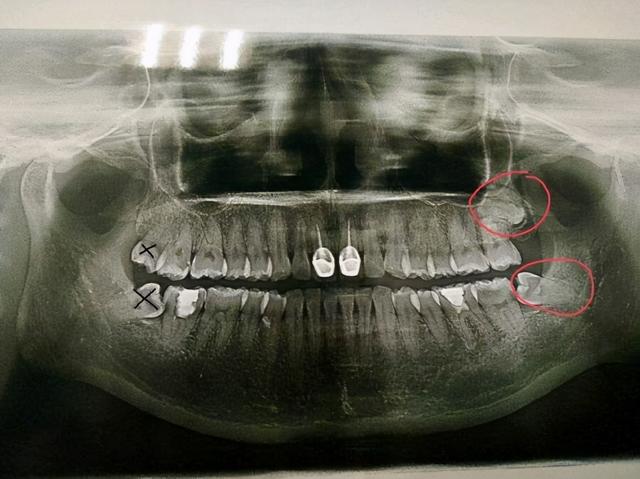

拔4颗智齿_口腔健康_什么值得买

图片尺寸864x1152